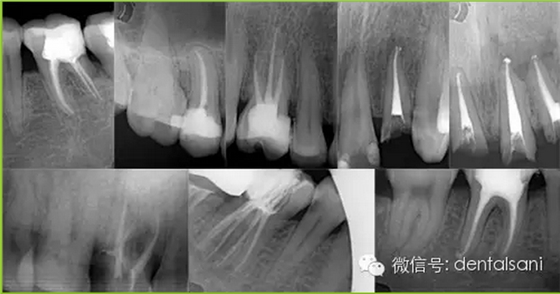

根管治療簡(jiǎn)單的說(shuō)就是通過(guò)根管的方式對(duì)于牙髓進(jìn)行一系列的治療,那么,現(xiàn)在根管治療已經(jīng)在口腔治療之中起到了非常重要的作用,一般是和補(bǔ)牙結(jié)合使用的,在整個(gè)根管治療過(guò)程之中需要注意什么呢?

適應(yīng)癥要選擇恰當(dāng)。根據(jù)病情,牙周狀況、X線片,病人的身體狀況等各方面因素來(lái)選擇,避免治療失敗。

4. 開(kāi)髓時(shí)要參照X線片,鉆針不宜進(jìn)入髓腔太深,以免損傷和磨穿髓底。如果底損傷后,則難以尋找根管口,有條件者用根管口擴(kuò)大器。萬(wàn)一髓底磨穿,可以用丁香油氧化鋅暫封穿底處后(穿底大,應(yīng)先用雙氧水、生理鹽水輕輕沖洗),再繼續(xù)擴(kuò)管。待炎癥消除后,再用磷酸鋅或銀汞合金將底充好,根管治療應(yīng)繼續(xù)進(jìn)行。另外,凡是別人治療過(guò)的、開(kāi)過(guò)髓的牙齒,接手之后必先拍X線片,因?yàn)橛袝r(shí)已經(jīng)穿底。